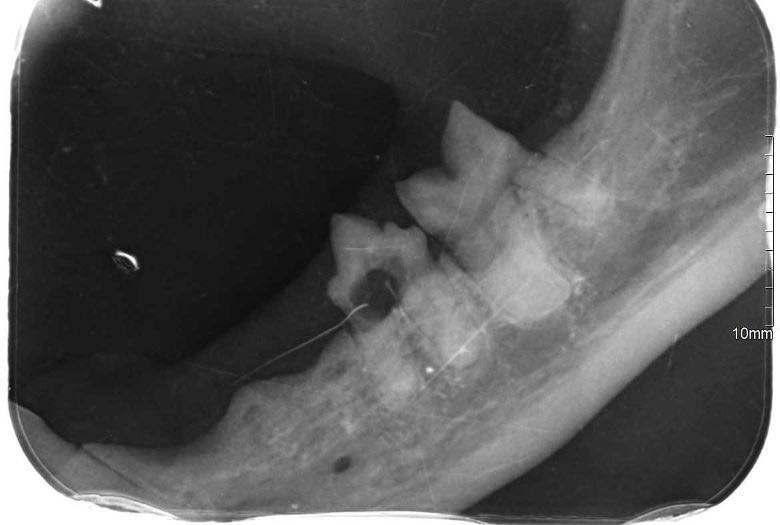

Zaczęło się od trudności z jedzeniem 🍽️, zgłoszonych przez tymczasową mamę, które skłoniły nas do dokładniejszej kontroli. Podczas wizyty weterynaryjnej okazało się, że zęby Loli wymagają pilnej interwencji. Została więc skierowana na zabieg stomatologiczny 🦷, w trakcie którego wykonano RTG jamy ustnej. Badanie wykazało sporo zmian – aż 8 zębów musiało zostać usuniętych.